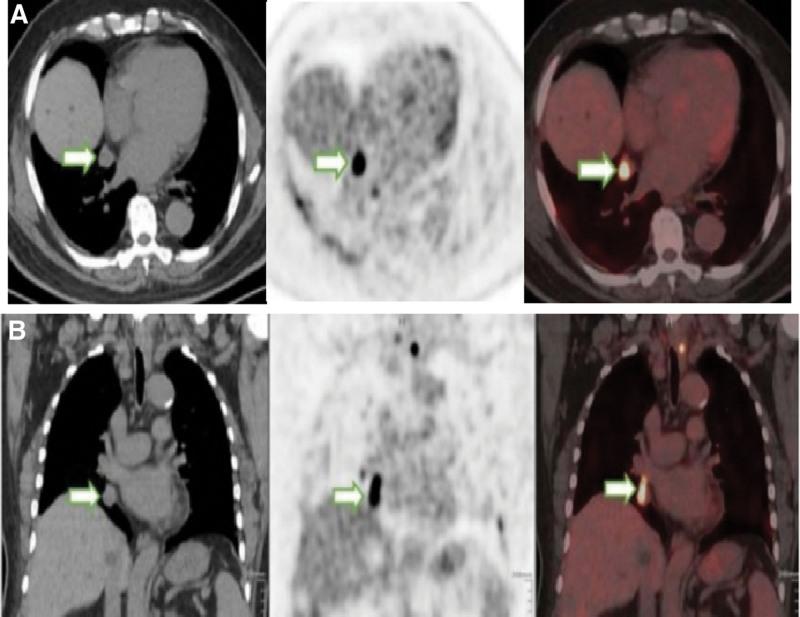

In clinical settings, an estimated 10% differentiated thyroid cancer (DTC) cases become radioactive iodide refractory (RAIR), which lack a molecular marker and have fewer treatment selections. A higher uptake of 18F-fluorodeoxyglucose (18F-FDG) might indicate poor prognosis for DTC. This study aimed to evaluate the clinical value of 18F-FDG psitron emission tomography/computed tomography (PET/CT) for the early diagnosis of RAIR-DTC and high-risk DTC. A total of 68 DTC patients were enrolled and underwent 18F-FDG PET/CT for the detection of recurrence and/or metastasis. 18F-FDG uptake was evaluated in patients with different postoperative recurrence risks or TNM stages and compared between RAIR and non-RAIR-DTC based on its maximum standardized uptake value and tumor/liver (T/L) ratio. The final diagnosis was judged by histopathology and follow-up data. Of 68 DTC cases, 42 were RAIR and 24 non-RAIR, with 2 not determined. A total of 263 of 293 lesions detected on 18F-FDG PET/CT were confirmed to be locoregional or metastatic after follow-up. The T/L ratio was significantly higher for RAIR than for non-RAIR (median 5.18 vs 1.44; P < .01) and also significantly higher in postoperative patients at high-risk of recurrence than at low to medium risk (median 4.90 vs 2.16; P < .01). 18F-FDG PET/CT exhibited a sensitivity of 83.3% and specificity of 87.5% for identifying RAIR, with a cutoff T/L value of 2.98. 18F-FDG PET/CT has the potential to diagnose RAIR-DTC early and identify the high-risk DTC. The T/L ratio is a useful parameter for the detection of RAIR-DTC patients.

在临床环境中,约有 10%的分化型甲状腺癌(DTC)病例会出现放射性碘难治(RAIR),这部分病例缺乏分子标志物,治疗选择较少。DTC 患者 18F-氟代脱氧葡萄糖(18F-FDG)摄取较高可能预示预后不良。本研究旨在评估 18F-FDG 正电子发射断层扫描/计算机断层扫描(PET/CT)对 RAIR-DTC 和高危 DTC 的早期诊断价值。共纳入 68 例 DTC 患者,均行 18F-FDG PET/CT 以检测复发和/或转移。根据最大标准化摄取值(SUVmax)和肿瘤/肝脏(T/L)比值,对不同术后复发风险或 TNM 分期的患者进行 18F-FDG 摄取评估,并根据 SUVmax 和 T/L 比值比较 RAIR 和非 RAIR-DTC 患者间的摄取差异。最终诊断通过组织病理学和随访数据判断。68 例 DTC 患者中,42 例为 RAIR,24 例为非 RAIR,2 例未确定。18F-FDG PET/CT 共检测到 293 个病灶,其中 263 个经随访证实为局部或远处转移。RAIR 患者的 T/L 比值明显高于非 RAIR(中位数 5.18 比 1.44;P < .01),且术后高复发风险患者的 T/L 比值也明显高于低至中复发风险患者(中位数 4.90 比 2.16;P < .01)。18F-FDG PET/CT 诊断 RAIR 的敏感度为 83.3%,特异度为 87.5%,截断 T/L 值为 2.98。18F-FDG PET/CT 具有早期诊断 RAIR-DTC 和识别高危 DTC 的潜力。T/L 比值是检测 RAIR-DTC 患者的有用参数。